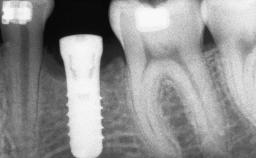

A 45-year-old woman with a completely edentulous maxilla was referred to evaluate the possibility of rehabilitation with an implant-supported prosthesis. This patient was healthy and a non-smoker. She had been wearing a maxillary complete denture opposing a natural mandibular dentition since her twenties. This situation had resulted in progressive resorption of the alveolar ridge, repeatedly creating a need for relining the denture. Twenty years later, despite multiple adaptations and the use of “glues” the denture was unstable and causing the patient psychological and functional discomfort.

| Bone Augmentation | Horizontal|Sinus Floor Elevation|Staged|Vertical |

| Augmentation Materials | Autogenous chips|Autogenous block(s) |